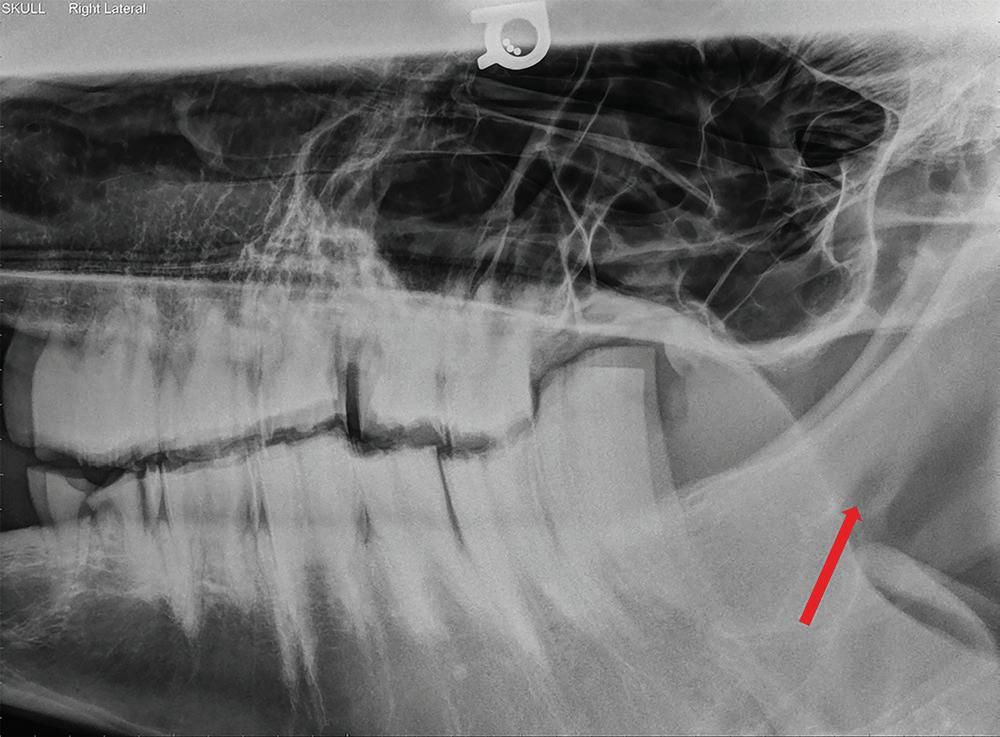

Blockade of the mental nerve at the mental foramen results in desensitization of the lower lip while advancement of a needle into the mandibular canal results in blockade of the mandibular alveolar nerve leading to desensitization of the ipsilateral incisors and premolars (Skarda et al. 2010; Rice 2017) (Figures 1.4 and 1.5). The block is achieved by elevating the depressor labii inferioris muscle and depositing

Figure 1.5 Lateral radiograph of a horse skull with severe dental disease. The mental foramen (red arrow) can be seen where the mental nerve exits to innervate the rostral aspect of the mandible. Mental nerve blockade can be used to desensitize the mandible rostral to the mental foramen to the level of the mandibular symphysis.

approximately 5 ml of local anesthetic with a 22 gauge, 1″ needle at the palpable ridge along the mandible at approximately the middle of the interdental space (Skarda et al. 2010).

A 25–20 gauge, 1–2.5″ needle and 3–10 ml of local anesthetic is described blockade of the mandibular alveolar nerve within the mandibular canal (Skarda et al. 2010; Rice 2017).